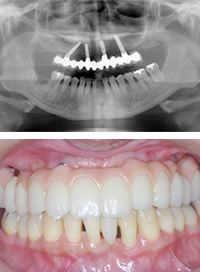

傾斜埋入でのオール・オン4

オール・オン4とは、4本のインプラントを片側もしくは上下両顎に埋め込むだけで口の中の歯全体を固定式の義歯にすることができるというインプラント治療法です。

傾斜埋入でのオール・オン4は上顎洞という解剖学的な空洞を避け、臼歯部に傾斜角をつけてインプラントを埋入し、固定式の上部構造を装着する傾斜埋入を応用した治療法です。

これによって、ブリッジに対する補綴支持を容易に得ることができ、個別に作製されたブリッジは術後数時間以内には機能するようになります。

取り外し式の「総入れ歯」に対して天然の歯のような快適な食生活や審美性の維持が可能になります。

最小4本のインプラントで全ての人工の歯を支えることを可能にし、症例によっては6本くらいのインプラントが必要な場合もあります。